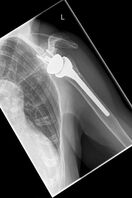

Bei der ersten Vorstellung klagte die 79 jährige Patientin über eine deutliche schmerzhafte linke Schulter und konnte diese kaum bewegen. Die Röntgenbilder zeigten einen fehlverheilten Bruch des Oberarmkopfes mit verschobenen Schrauben nach auswärtiger Nagelosteosynthese. Die operative Behandlung erfolgte mit einem inversen künstlichen Schultergelenk mit einem verlängerten zementfreien Schaft. Die erhebliche Vernarbung stellt eine besondere Herausforderung sowohl innerhalb der Operation als auch in der nachfolgenden Physiotherapie dar.